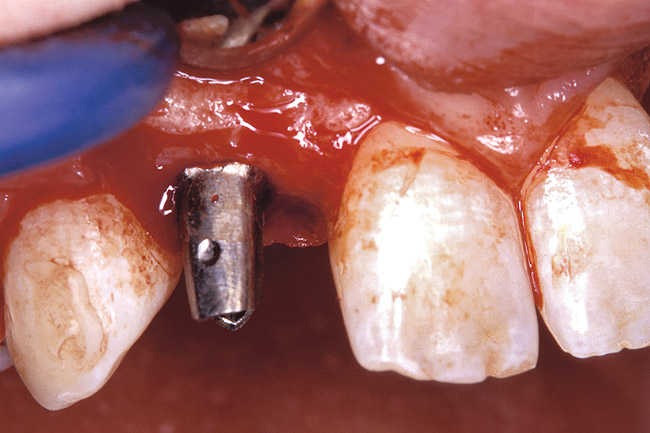

Figure 33  VIRTUAL PLANNING AND SURGERY After the osteotomies were completed, the implants were placed.

Figure 33

Figure 34  VIRTUAL PLANNING AND SURGERY After the osteotomies were completed, the implants were placed.

Figure 34